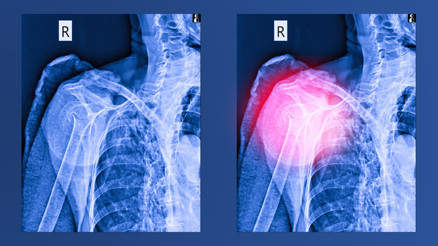

#Prenses RajwaJessica Lane, beş aylık hamileyken doktorlar omzundaki ve kolundaki ağrının hamilelikten kaynaklanan gerginlikten dolayı oluşan kas ağrısı olduğunu söylediler. Ancak doğumdan beş hafta sonra, bebeğinin araba koltuğunu taşırken bir çıtırtı duydu. Bunun için doktora gittiğinde 31 yaşındaki yeni anne kemik kanseri olduğunu öğrendi. Peki yaşadığımız hangi kemik ağrılarını dikkate almalıyız? Ortopedi Uzmanı Op. Dr. Hasan Mehmet Hüseyin ile konuştuk